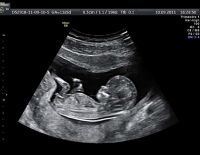

Siêu âm 2D là hình thức siêu âm dành cho các mẹ bầu ở những tuần đầu của thai kỳ. Đây là phương pháp siêu âm cũ nhưng vẫn được áp dụng nhiều hiện nay. Khi siêu âm 2D các mẹ bầu vẫn nắm được...